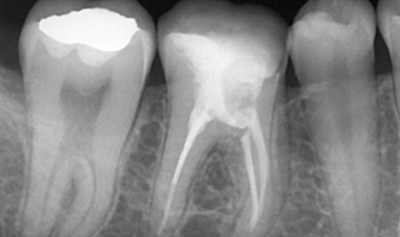

Radiología & Diagnóstico

Endodoncia